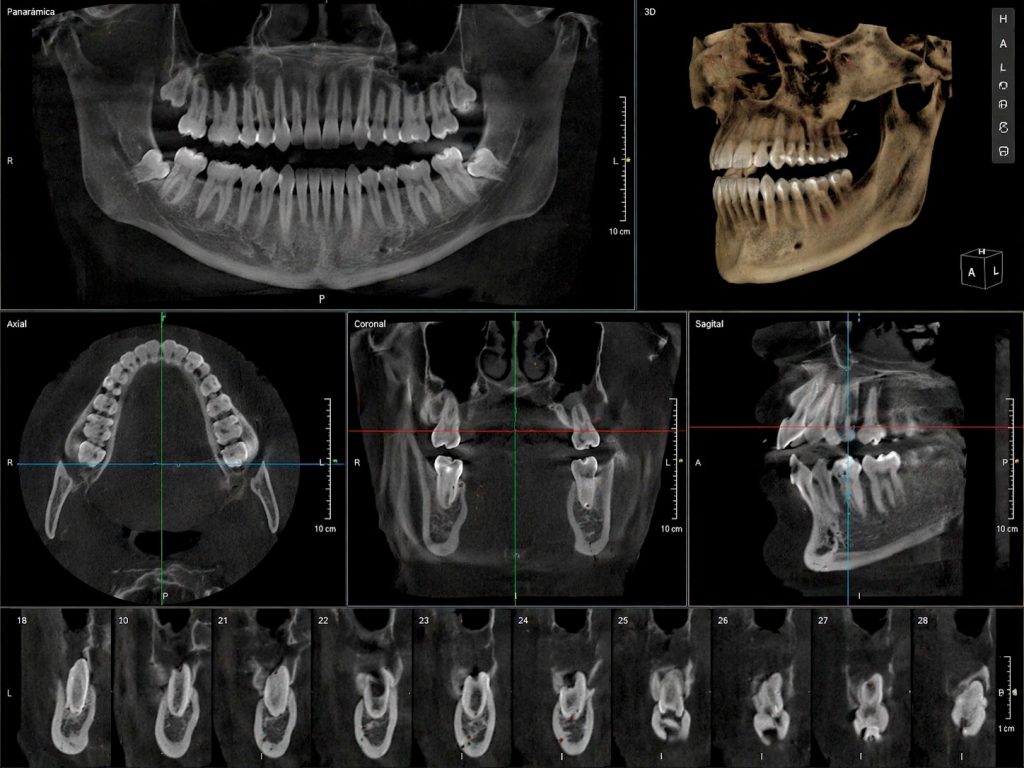

La radiografia 3D o CBCT és una tecnologia de diagnòstic per imatge que genera una reconstrucció tridimensional de les estructures dentals, òssies i nervioses del pacient.

A diferència de les radiografies convencionals, el CBCT permet visualitzar:

• Dents des de tots els angles

• Os maxil·lar i mandibular amb gran detall

• Nervis i estructures anatòmiques sensibles

• Sins maxil·lars

• Posició exacta de peces dentals incloses